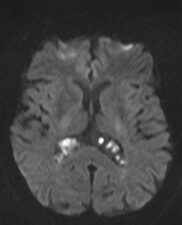

Son pseudolesiones frecuentemente observadas en estudios de neuroimagen.

Sus principales características son:

✔ Lesiones intraventriculares

✔Bilaterales

✔65% restringen en la secuencia de difusión

✔ Realce variable posterior a la administración de medio de contraste

✔ No hay edema del parenquima adyacente

NO DEBEN CONFUNDIRSE CON LESIONES TUMORALES INTRAVENTRICULARES!!!!